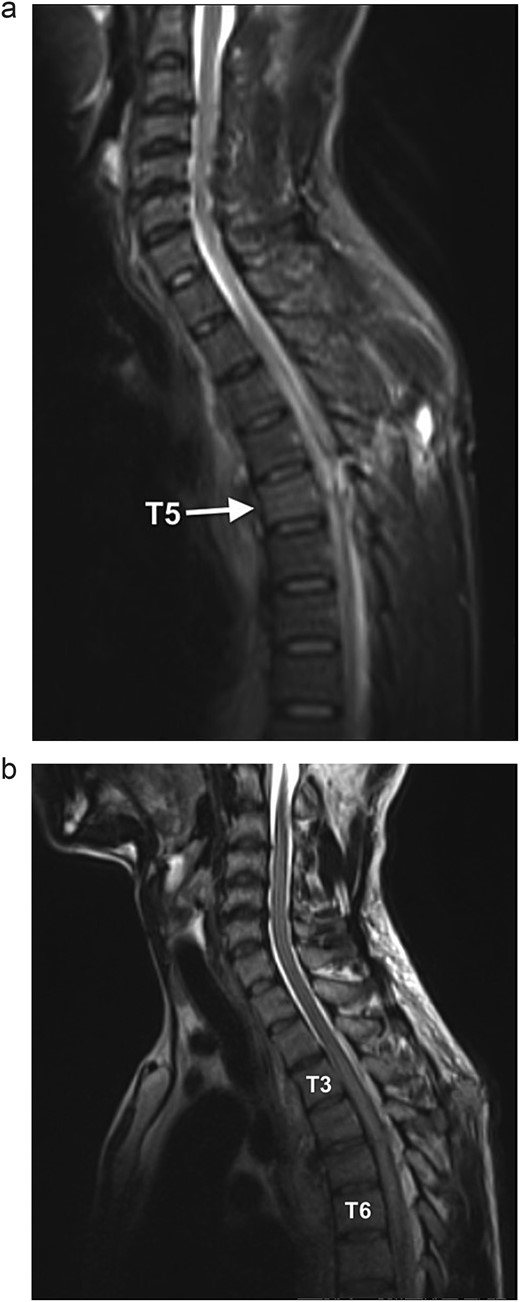

On neurological examination, the patient was suspected of having Brown–Sequard syndrome, as power and light touch sensation was reduced in the right lower limb, with reduced sensation over the right lower abdomen. Furthermore, there was decreased pain sensation in the left lower limb. He had normal bladder function and normal sensation over the sacral area. The patient was reviewed by the Neurosurgical team and referred for an magnetic resonance imaging (MRI) of the spine. The MRI demonstrated a penetrating injury to the mid-thoracic spine with a right hemicord transection at the level of T5 (Fig. 1a). There was an associated right spinal epidural hematoma with resultant compression of the cord and cord oedema (Figs 1b and 2a). The Neurosurgery team elected to manage the injury conservatively.

(a) Sagittal STIR MR shows a hyperintense signal along the dorsal mid-thoracic soft tissue wound tract, extending into the spinal canal with T5 level cord disruption and T5 vertebral body marrow oedema. (b) Sagittal T2WI MR demonstrates cord oedema as a hyperintense signal of the central cord (T3 to T6 level).